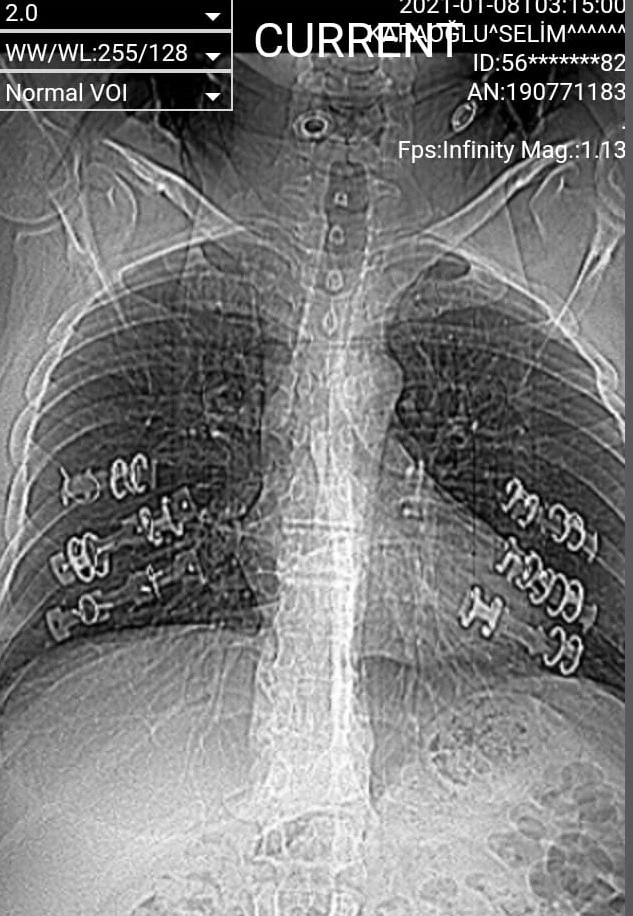

İstanbul Sultanbeyli’de oturan Selim Karaoğlu, geçen yıl şiddetli öksürük şikâyetiyle hastaneye başvurdu. Covid-19 testi yapılan şahsın sonucu negatif çıktı. Hasta evine gönderildi ancak öksürükleri daha da şiddetlendi, vücudunda ağrılar başladı. Farklı bir hastaneye giden Karaoğlu’nun çekilen tomografisinde 6 kaburgasının kırık olduğu anlaşıldı. Şahsın vücuduna platin ve teller takıldı.

Bu tedavinin bir işe yaramadığını belirten Karaoğlu, vücudunda kanamalar başladığını belirterek “Beş ay boyunca kırık kaburgalarla gezdim. Ardından 4 kere ameliyat oldum. Ancak taktıkları platinler tutmadı, bağladıkları tel koptu. Sırt bölgemde şişlikler oluştu. Vücudum sürekli kanıyor” dedi.